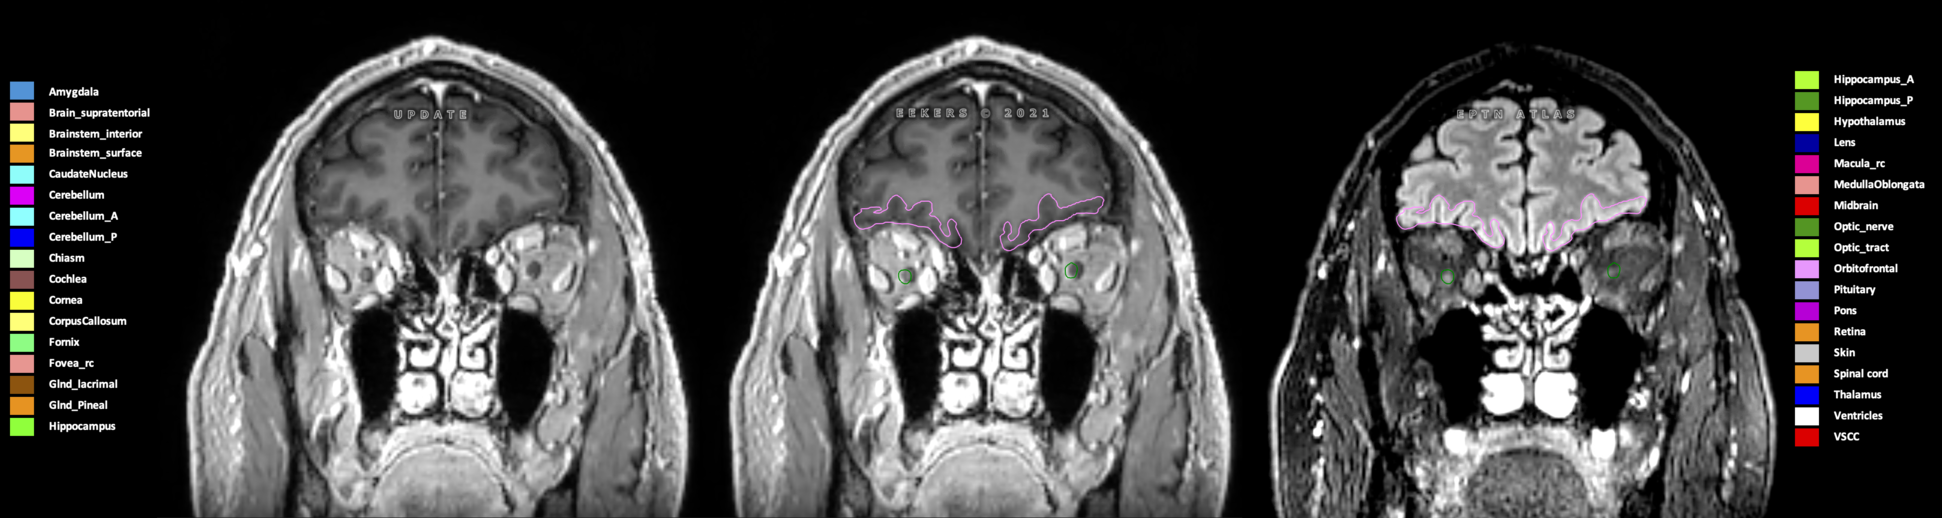

Eekers et al. have published an international neurological atlas for contouring of organs at risk in consensus with the European Particle Therapy Network (EPTN) in 2018 and an update in 2021. The purpose of this consensus atlas is to decrease inter- and intra-observer variability in delineating OARs relevant for neuro-oncology.

Included are all OARs known to be relevant for radiation-induced toxicity in neuro-oncology: brain, brainstem (midbrain, pons, medulla oblongata), chiasm, cerebellum (anterior & posterior), cochlea, cornea, hippocampus (anterior & posterior), hypothalamus, lens, lacrimal gland, optic nerve, pituitary, skin, and vestibular & semicircular canals. To further facilitate research on cognition, vision and radiological changes after irradiation of the brain, potential clinically-relevant OARs are included: amygdala, caudate nucleus, cerebellum (anterior & posterior), corpus callosum, fornix, macula, optic tract, orbitofrontal cortex, periventricular space (PVS), pineal gland, and thalamus.

Three-dimensional delineation of the 25 consensus OARs for neuro-oncology are shown on CT (WW/WL 120/40, 3000/600), 3T MR images, (T1Gd, T2FLAIR 1mm) and 7T MR (MP2RAGE 0.7 mm). All are presented in transversal, sagittal and coronal view.